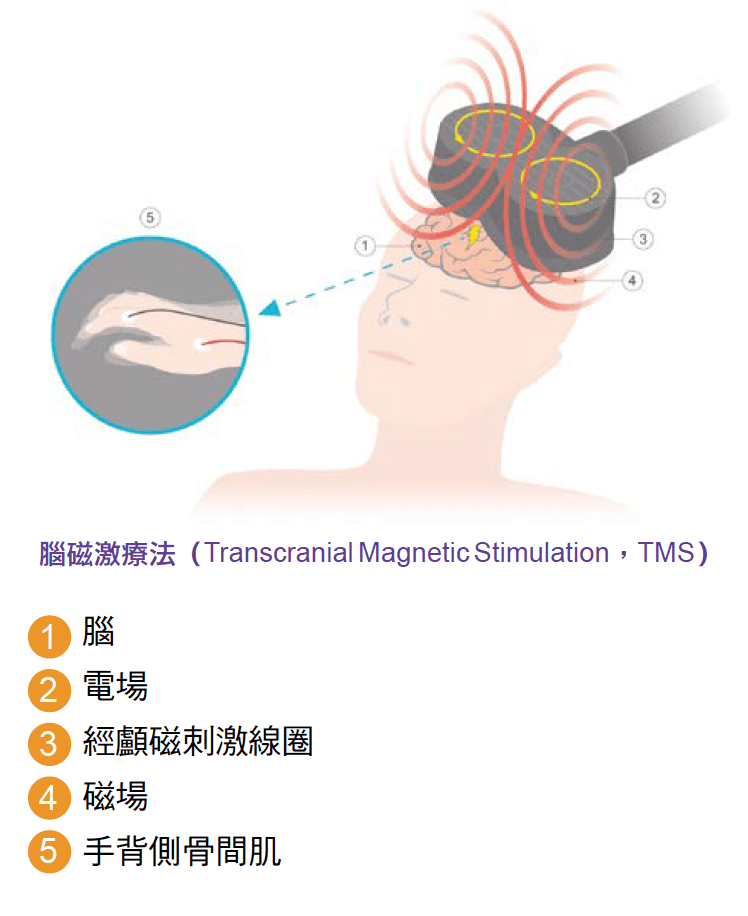

In recent years, there have been many scientific and technological advances in medicine, and doctors can use some specialized drugs and physical methods, such as magnetic fields (Transcranial Magnetic Stimulation, TMS) or direct current (transcranial direct current stimulation transcranial direct current stimulation, tDCS) to help damaged brain nerves repair, the effect is very significant.

After more than three months of intensive treatment and rehabilitation, Ms. Leung was still in a deep coma despite being able to save her life. The doctor told the family that Ms. Leung was likely to become disabled or commonly known as a vegetative stroke survivor in the future, and suggested that the family transfer her to a nursing home and plan long-term care in a private sector after discharge. During staying at the nursing home, Ms. Leung condition did not improve, but also suffer from complications caused by long-term coma and bed resting. In order to get a better chance of recovery, her family transferred her to a private hospital for further stroke rehabilitation. After six weeks of intensive stroke rehabilitation treatments such as drugs, physical therapy, acupuncture, and DC stimulation (transcranial DIRECT current stimulation), Ms Leung finally woke up and regain her speech, can eat and walk. After being discharged from the hospital, Ms. Leung continue to receive medication, physical therapy and brain TMS treatment, and improved swallowing, hand and foot coordination, and walking ability. Three years on, Ms. Leung has not become the vegetative person, but a stroke survivor with mild to moderate disabilities, and she and her family have moved to the UK to enjoy life.

After three months of hospitalized with stroke rehabilitation, through specialized drugs, physiotherapy, acupuncture, DIRECT current stimulation treatment and brain TMS treatment, Li’s right foot strength was significantly restored, from complete inability to move, to the right foot ability to walk with the assistance of equipment, and the language ability to communicate and talk fluently with her children. After being discharged from the hospital, Ms. Li continued to receive medication, brain TMS therapy and physical therapy, and her walking ability and language skills continued to improve. The main reason for Li’s cerebral vascular stroke is caused by poor control of high cholesterol. She needs to take high-dose cholesterol drugs and platelet drugs for a long time to prevent cerebral blood vessels from degenerate and prevent another stroke. Today Ms. Li is only moderately disabled, able to use cane to walk on her own, and can continue to live at home under the care of a domestic helper.

Through medication, TMS or direct current therapy, the purpose is to stimulate injured brain cells, to promote the regeneration of nerve cell function, so that the original loss of nerve function of stroke patients can be restored.